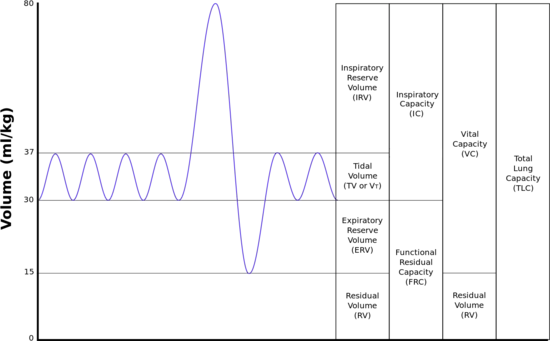

The lungs expand and contract during the breathing cycle, drawing air in and out of the lungs. The volume of air moved in or out of the lungs under normal resting circumstances (the resting tidal volume of about 500 ml), and volumes moved during maximally forced inhalation and maximally forced exhalation are measured in humans by spirometry.[12] A typical adult human spirogram with the names given to the various excursions in volume the lungs can undergo is illustrated below (Fig. 3):

Not all the air in the lungs can be expelled during maximally forced exhalation(ERV). This is the residual volume(volume of air remaining even after a forced exhalation) of about 1.0-1.5 liters which cannot be measured by spirometry. Volumes that include the residual volume (i.e. functional residual capacity of about 2.5-3.0 liters, and total lung capacity of about 6 liters) can therefore also not be measured by spirometry. Their measurement requires special techniques.[12]

During exhalation, the diaphragm and intercostal muscles relax. This returns the chest and abdomen to a position determined by their anatomical elasticity. This is the "resting mid-position" of the thorax and abdomen (Fig. 7) when the lungs contain their functional residual capacity of air (the light blue area in the right hand illustration of Fig. 7), which in the adult human has a volume of about 2.5–3.0 liters (Fig. 3).[6] Resting exhalation lasts about twice as long as inhalation because the diaphragm relaxes passively more gently than it contracts actively during inhalation.

The volume of air that moves in or out (at the nose or mouth) during a single breathing cycle is called the tidal volume. In a resting adult human, it is about 500 ml per breath. At the end of exhalation, the airways contain about 150 ml of alveolar air which is the first air that is breathed back into the alveoli during inhalation.[10][20] This volume air that is breathed out of the alveoli and back in again is known as dead space ventilation, which has the consequence that of the 500 ml breathed into the alveoli with each breath only 350 ml (500 ml - 150 ml = 350 ml) is fresh warm and moistened air.[6] Since this 350 ml of fresh air is thoroughly mixed and diluted by the air that remains in the alveoli after a normal exhalation (i.e. the functional residual capacity of about 2.5–3.0 liters), it is clear that the composition of the alveolar air changes very little during the breathing cycle (see Fig. 9). The oxygen tension (or partial pressure) remains close to 13-14 kPa (about 100 mm Hg), and that of carbon dioxide very close to 5.3 kPa (or 40 mm Hg). This contrasts with composition of the dry outside air at sea level, where the partial pressure of oxygen is 21 kPa (or 160 mm Hg) and that of carbon dioxide 0.04 kPa (or 0.3 mmHg).[6]

During heavy breathing, exhalation is caused by relaxation of all the muscles of inhalation. But now, the abdominal muscles, instead of remaining relaxed (as they do at rest), contract forcibly pulling the lower edges of the rib cage downwards (front and sides) (Fig. 8). This not only drastically decreases the size of the rib cage, but also pushes the abdominal organs upwards against the diaphragm which consequently bulges deeply into the thorax (Fig. 8). The end-exhalatory lung volume is now well below the resting mid-position and contains far less air than the resting "functional residual capacity". However, in a normal mammal, the lungs cannot be emptied completely. In an adult human, there is always still at least 1 liter of residual air left in the lungs after maximum exhalation.[6]